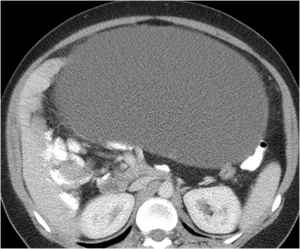

A 56-year-old Vietnam veteran man was admitted with a three-day history of worsening abdominal pain progressing into an acute abdomen. He had past medical history of Hepatitis C, diabetes mellitus, high blood pressure and chronic abdominal pain of unknown etiology. There was no gross bowel pathology by upper endoscopy or colonoscopy early the year of admission.